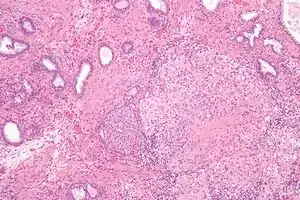

| Micrograph showing a granulomatous prostatitis due to BCG treatment for bladder cancer. H&E stain. | |

Noticeable destruction of Acini, surrounded by epitheloid cells, giant cells, lymphocytes, plasma cells and dense fibrosis.[2]